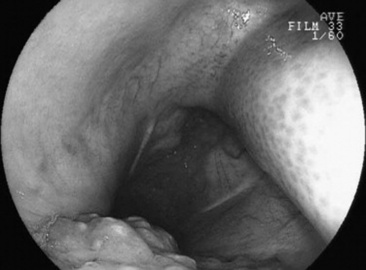

C. coronatus is a saprophytic fungus that causes granulomatous lesions of the upper respiratory tract in horses. Single to multiple granulomatous lesions in the nasal passages, trachea, or soft palate can be observed endoscopically (Fig. 31-19). Histologic appearance of conidiobolomycosis is similar to that of pythiosis and basidiobolomycosis. Hyphae of C. coronatus are thin-walled, highly septate, and irregularly branched (see Table 31-5).356 The lesions typically have large numbers of eosinophils and fewer macrophages, neutrophils, plasma cells, and lymphocytes surrounding hyphae. Definitive diagnosis is based on microbiologic culture, immunodiffusion, or PCR.357 Detection of serum antibodies by immunodiffusion is considered highly sensitive and specific354,358 and can be used to monitor response to treatment.358 A nested PCR Pythium assay has also been used to identify C. coronatus.359

image

Fig. 31-19 Endoscopic image of mycotic granulomas caused by Conidiobolus coronatus in the nasopharynx of a horse.

Conidiobolomycosis lesions can be treated with surgical excision, laser therapy, cryotherapy, or long-term administration of iodides or antifungals.342,354,357 Amphotericin B has been administered intralesionally or topically in combination with dimethyl sulfoxide (DMSO) to treat C. coronatus.342-345 It is important to remember that long-term therapy and reevaluation are essential, as recurrence can occur.345 Oral fluconazole was successful in treating two pregnant mares with nasal conidiobolomycosis.360 A vaccine using C. coronatus antigen from broth cultures was unsuccessful in treating seven horses with conidiobolomycosis.357